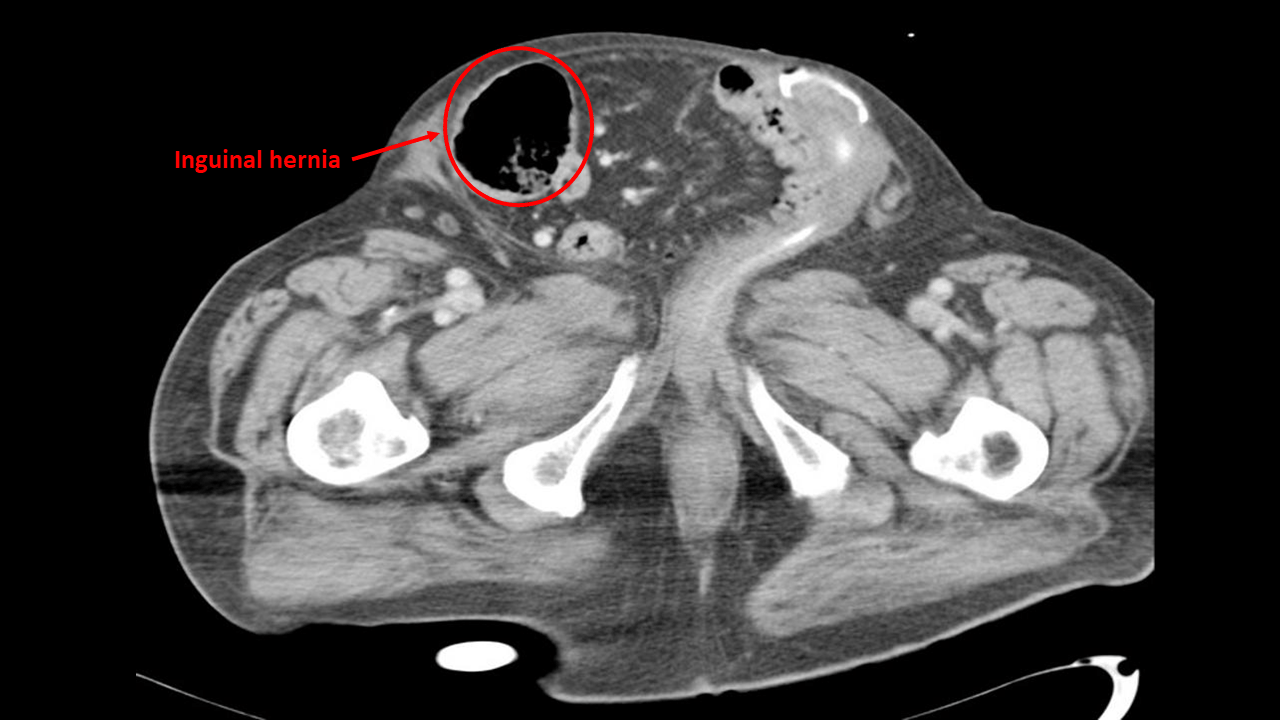

From wikidoc.org

Inguinal hernia CT wikidoc What Does A Cat Hernia Feel Like If your cat is exhibiting any of these symptoms, it’s time to see the vet: The symptoms associated with hernias in cats vary depending on the type of defect. It is located just under the ribcage on a cat’s underside,. When caught early on, usually cat hernias aren’t serious, however they may become fatal if they’re left untreated. Hernias in. What Does A Cat Hernia Feel Like.